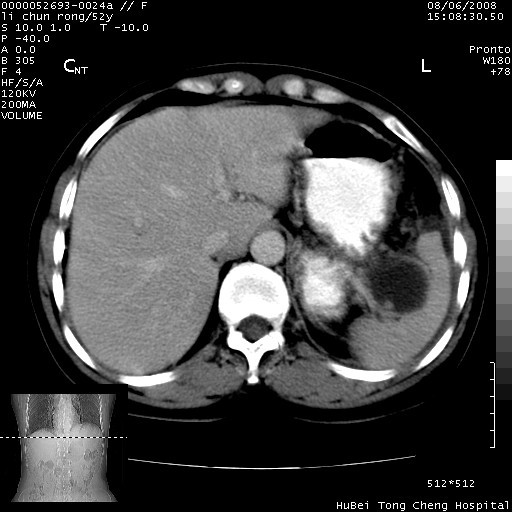

以下是引用云翔在2008-8-7 6:20:00的发言:[br]胰尾部囊性病变,考虑假囊肿,结合实验室检查疾病史

以下是引用zjzjr在2008-8-7 8:38:00的发言:[br]支持胰腺炎伴假囊肿形成,左肾小囊肿.少量腹水.

以下是引用随光逐影在2008-8-7 9:12:00的发言:[br]1)考虑胰腺炎伴假性囊肿形成可能性大;胰腺囊腺瘤待排。2)左肾小囊肿。3)少量腹水。